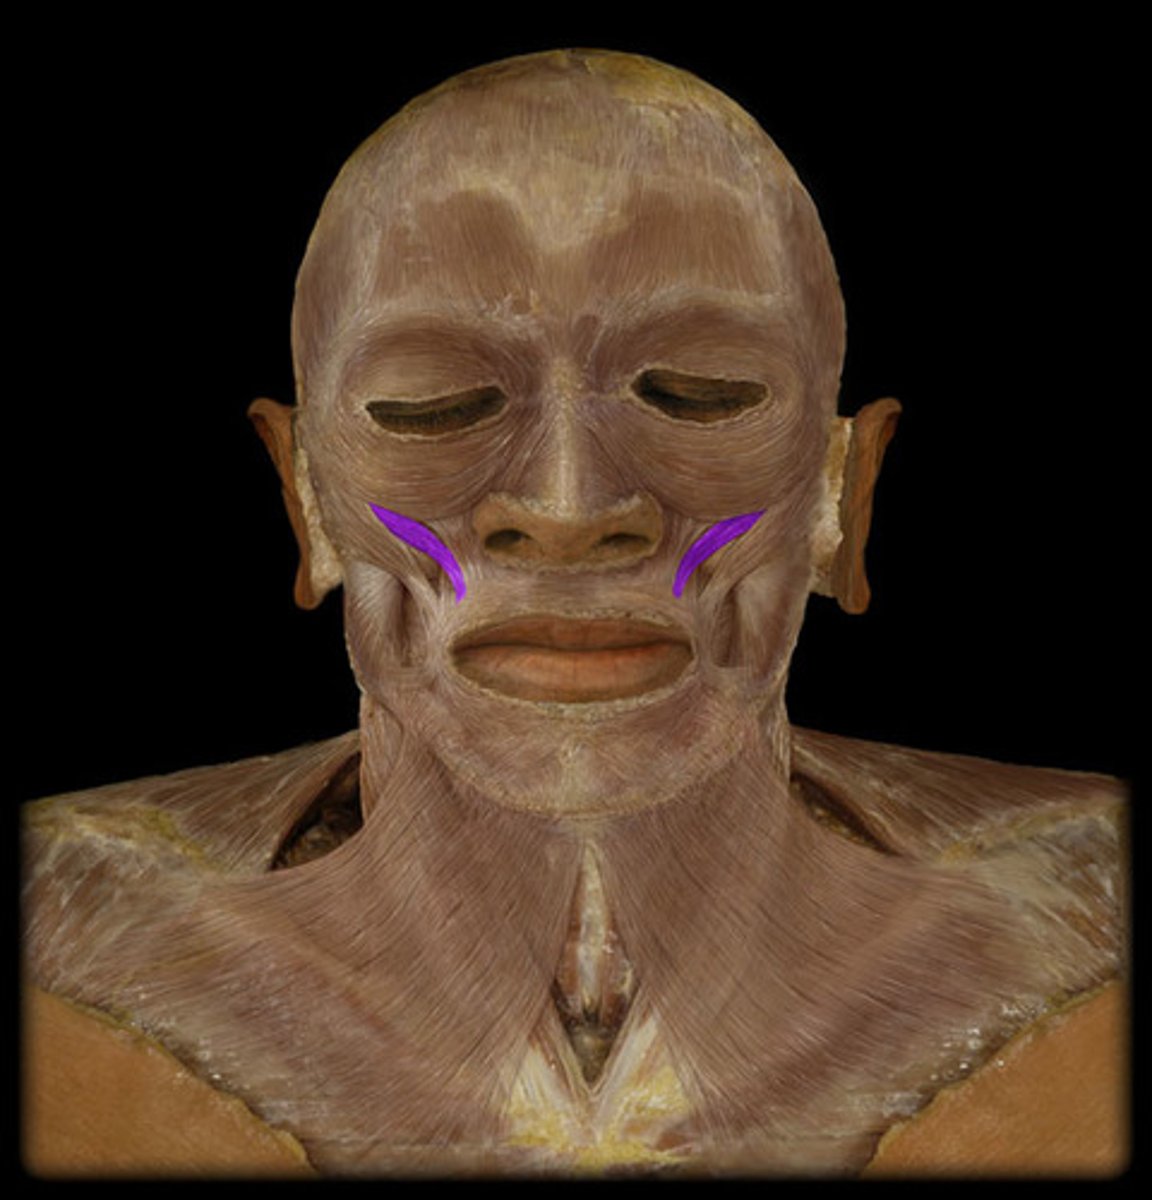

Zygomaticus major m.

Origin: Zygomatic arch

Insertion: Corner of mouth

Action: Elevate (smile)

Zygomaticus minor m.

Origin: Zygomatic arch

Insertion: Corner of mouth

Action: Elevate (smile)